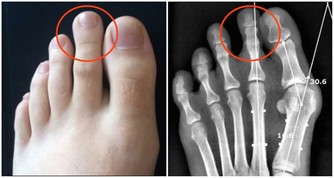

隨著年齡漸長,發生骨質疏鬆的機會也跟著增加,往往一不注意就落入骨質脆弱的環節里。

治療骨質疏鬆的藥物有許多種類,只要照醫囑按時使用並定期回診追蹤,

就有可能控制得宜,但是也有些病人按時服藥卻仍不見骨質疏鬆改善。

其實,骨質疏鬆和平時所用藥物也有關係,藥物長期使用之下可能造成骨質漸漸流失。

以下藥品有可能造成骨質流失,

因此若平時有長期使用以下藥品且確診為骨質疏鬆症患者,

建議與醫師聯繫,視情況調整用藥,才能做個有「骨氣」的人。

常見可能造成骨質疏鬆的藥物

1、增加維生素D的代謝:Phenytoin(癲癇治療)、Phenobarbital(癲癇治療)。

2、增加骨代謝:Valproicacid(精神科用藥)、Cyclosporin(控制器官移植後排斥作用)、Heparin(血栓性栓塞症及其預防)。

3、減少骨生成:Ifosfamide(抗癌藥)、Prednisolone(緩解發炎及過敏癥狀)。

4、減少血清鈣的濃度:Carbamazepine(癲癇治療、三叉神經痛)。